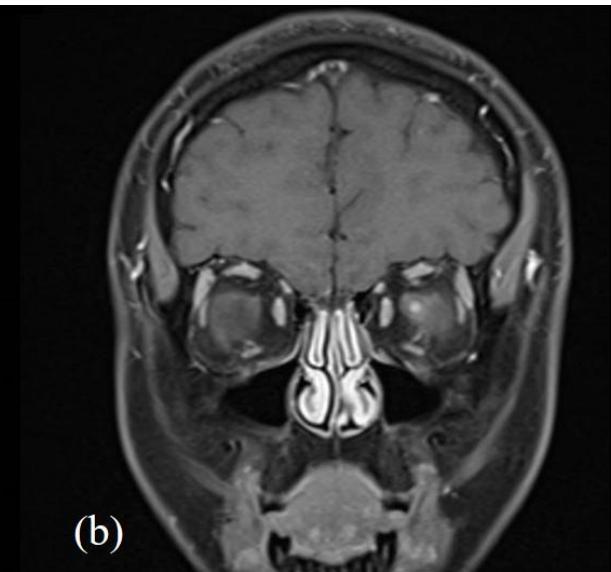

The patient's infectious screen was negative. This included; Quantiferon-TB Gold, Syphilis, Bartonella henselae immunoglobulin G (IgG)/immunoglobulin M (IgM), human immunodeficiency virus (HIV) antigen and antibody (Ag/Ab), cytomegalovirus (CMV) IgG/IgM, Toxoplasma IgG/IgM and Leptospiral IgM enzyme-linked immunosorbent assay (ELA). Serum angiotensin converting enzyme (ACE) and chest x-ray were normal. Lyme disease serology (Borrelia burgdorferi) was not tested as he had not travelled outside of NZ. Bartonella henselae serology was negative when sequentially tested on initial presentation as well as 4 and 8 weeks later. He had a normal full blood count, liver function, renal function, serum folate and B12. His antinuclear antibodies (ANA) were weakly positive and inconclusive with negative extractable nuclear antigen (ENA), antineutrophil cytoplasmic antibodies (ANCA) and double-stranded deoxyribonucleic acid 40 (dsDNA). Neuromyelitis optica (NMO) IgG antibodies were initially positive however negative on repeat testing 4 weeks

later including negative myelin oligodendrocyte glycoprotein (MOG) antibodies. Magnetic resonance imaging (MRI) of the head, orbits and spine with gadovist contrast were consistent with left retrobulbar optic neuritis without intracranial or spinal involvement (figure 3).

Figure 3: MRI head and orbits with (a); T2 axial TSE FLAIR sequence and (b); T1 coronal TSE Dixon sequence with contrast. Focal enhancement of the anterior margin of the left optic nerve at its junction with the globe is demonstrated without other demyelination or parenchymal intracranial pathology.